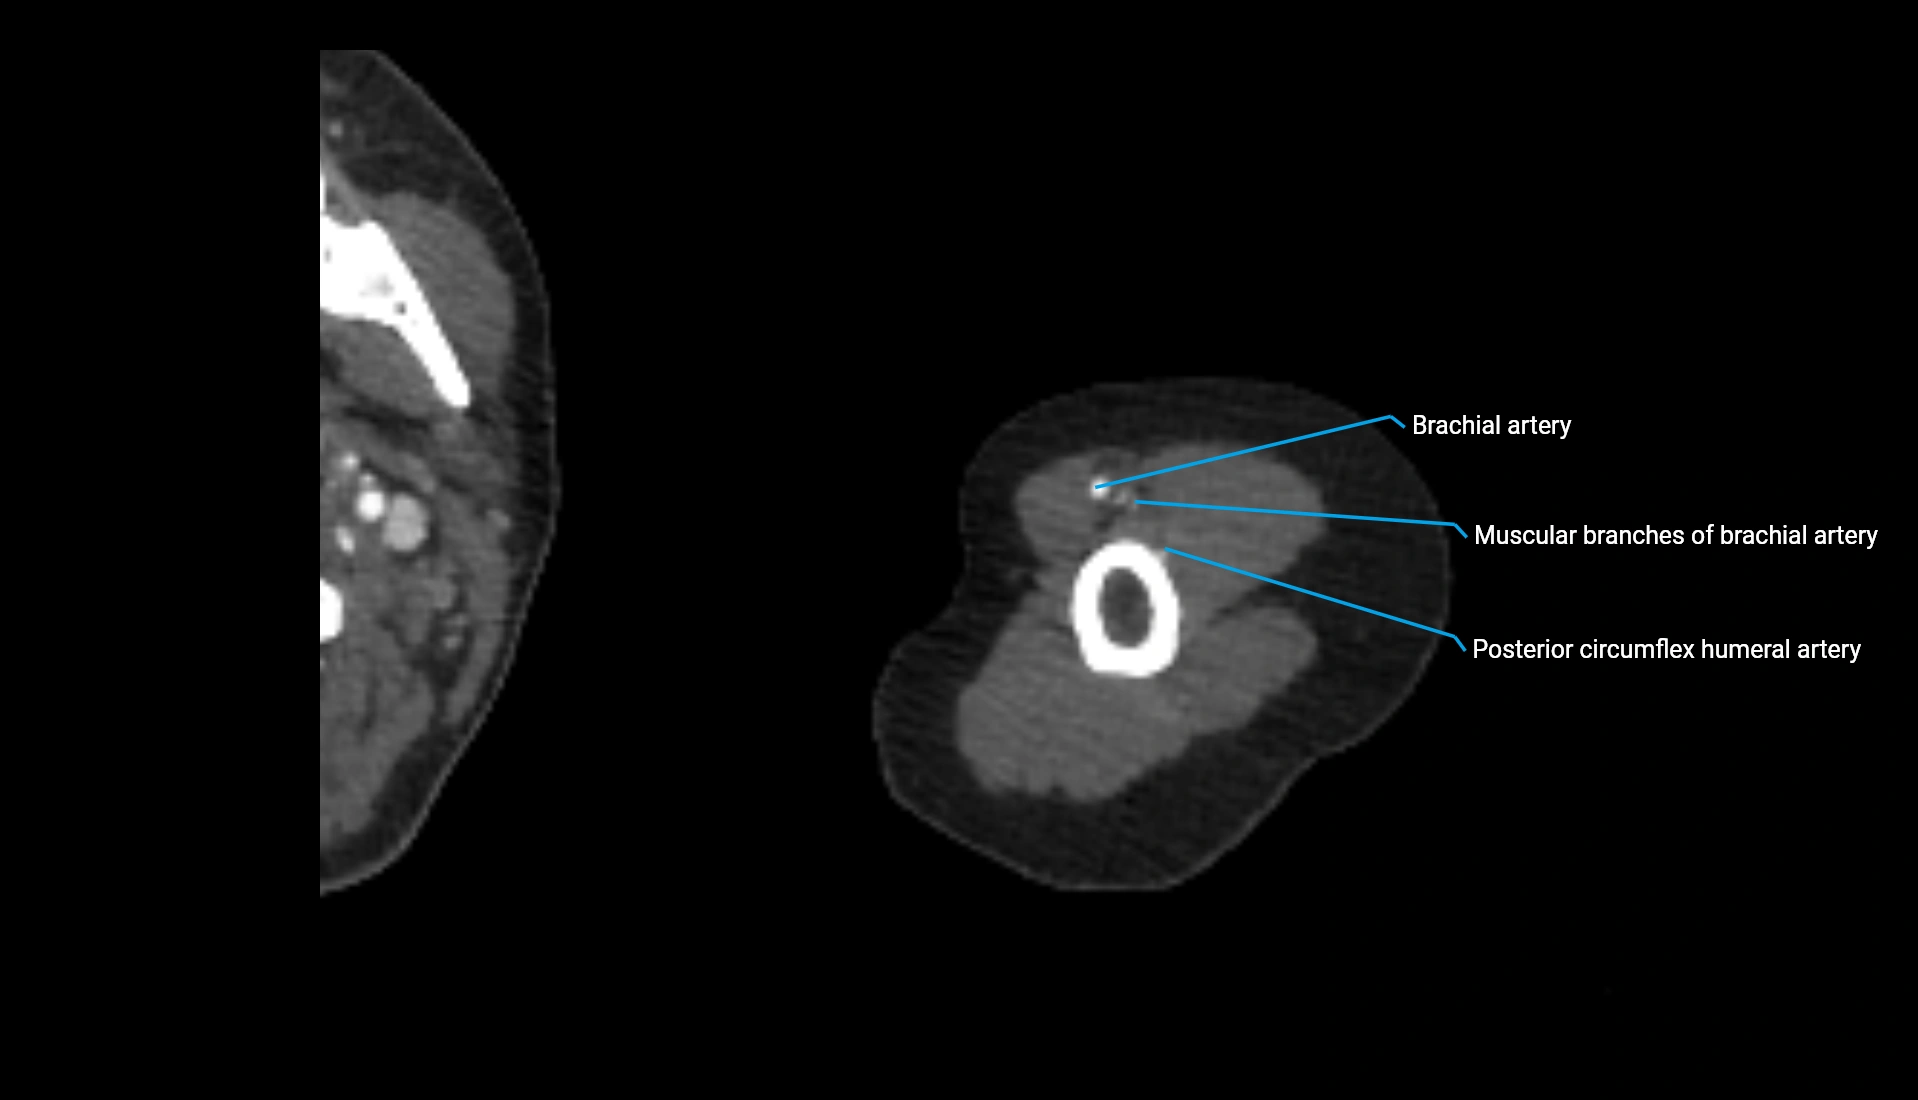

CT Appearance

Non-Contrast CT:

• Cortex: High-density, sharply defined

• Subchondral bone: Dense cancellous matrix

• Articular surface: Smooth concave contour articulating with the capitellum

• Excellent for evaluating bone integrity, alignment, and subtle fractures

Post-Contrast CT:

• Bone: No enhancement

• Joint capsule and synovium: Mild enhancement outlining the joint

• Improves contrast between soft tissues and bony margins

• Useful in detecting subtle joint abnormalities or postoperative changes